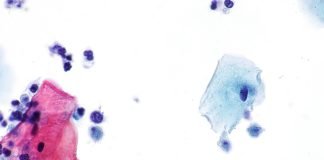

Tricomonaza, o infectie transmisa prin contact sexual

Tricomonaza reprezinta o infectie parazitara contagioasa care se transmite prin contact sexual. Nu este o infectie grava insa de obicei (cam la 70% din...